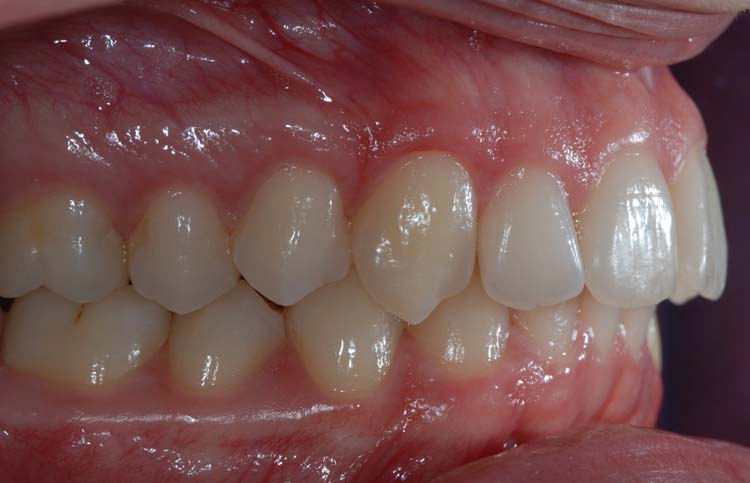

Caso clinico 1

Caso clinico 2

Caso clinico 3

Caso clinico 4

Caso clinico 5

Caso clinico 6